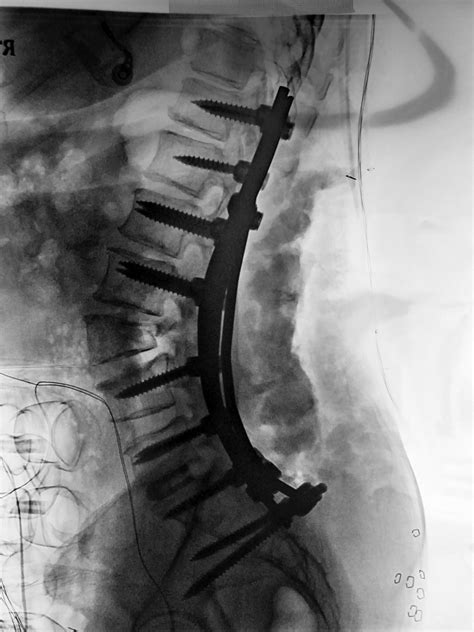

Introducing the ADR Spine Top Doctors in Arthroplasty Program ...